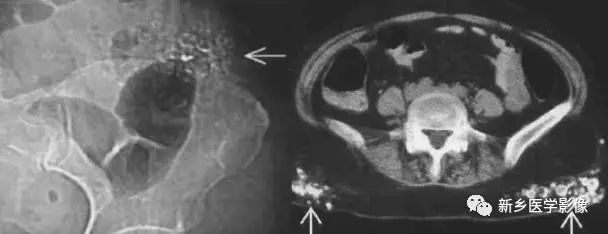

常见于尿路阳性结石,可以发生在尿路任何位置,如肾结石、输尿管结石及膀胱结石